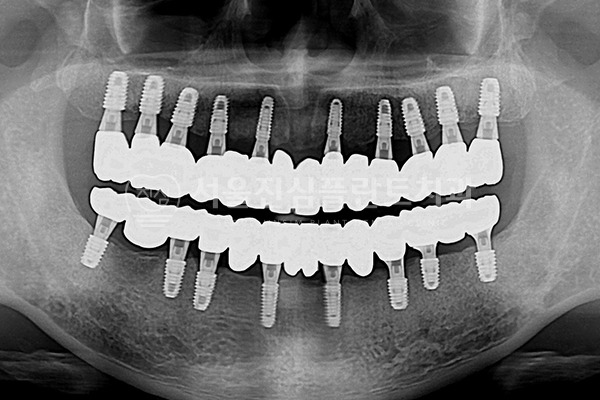

전체 임플란트

-

BEFORE

AFTER

발치즉시 임플란트 + 전체 임플란트 + 즉시 부하